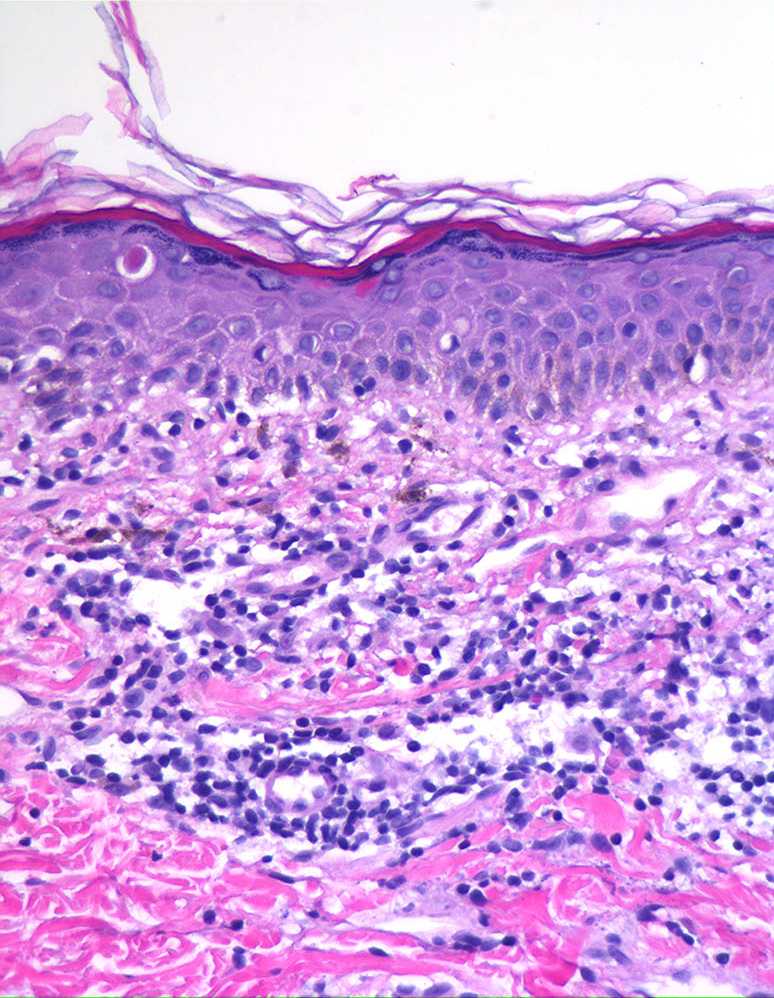

Ashy dermatosis = التهاب الجلد الرمادي